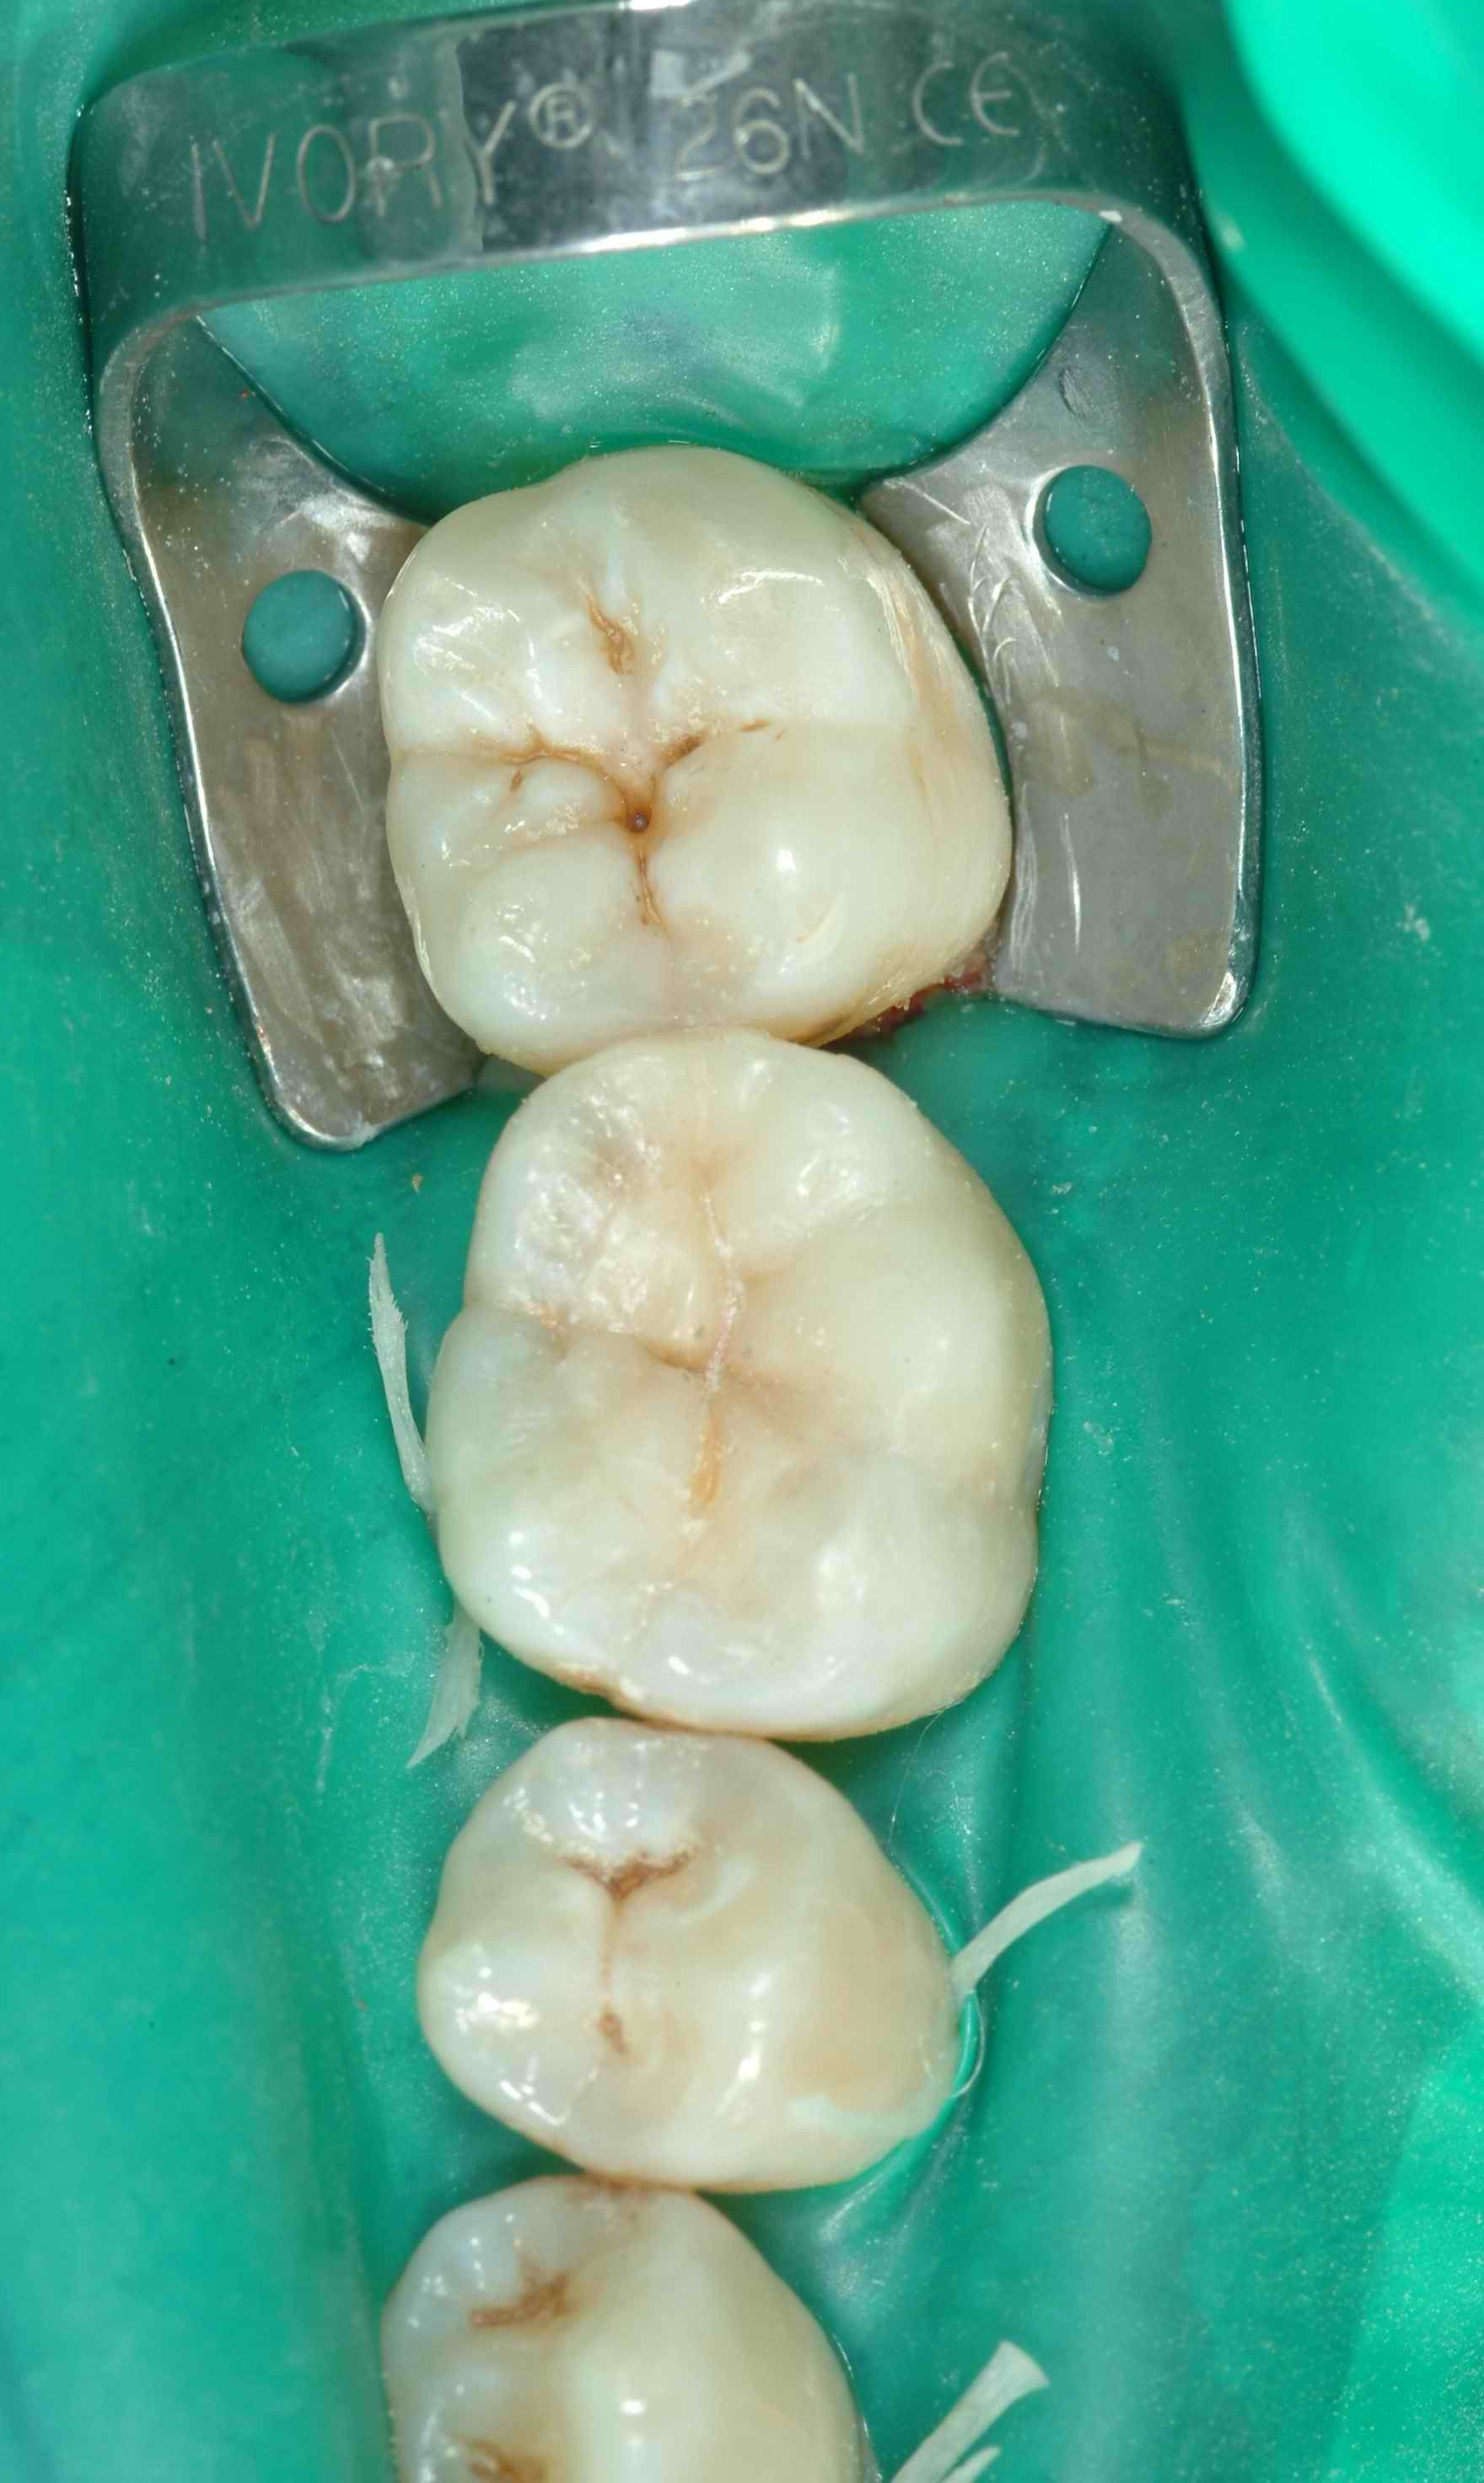

Conservativa indiretta

Lo specialista effettua interventi di conservativa indiretta, inclusa la sostituzione delle vecchie amalgame con restauri in composito. Questa tecnica permette di rimuovere le carie e riparare i denti danneggiati, utilizzando materiali estetici e biocompatibili che si integrano perfettamente con il dente naturale.